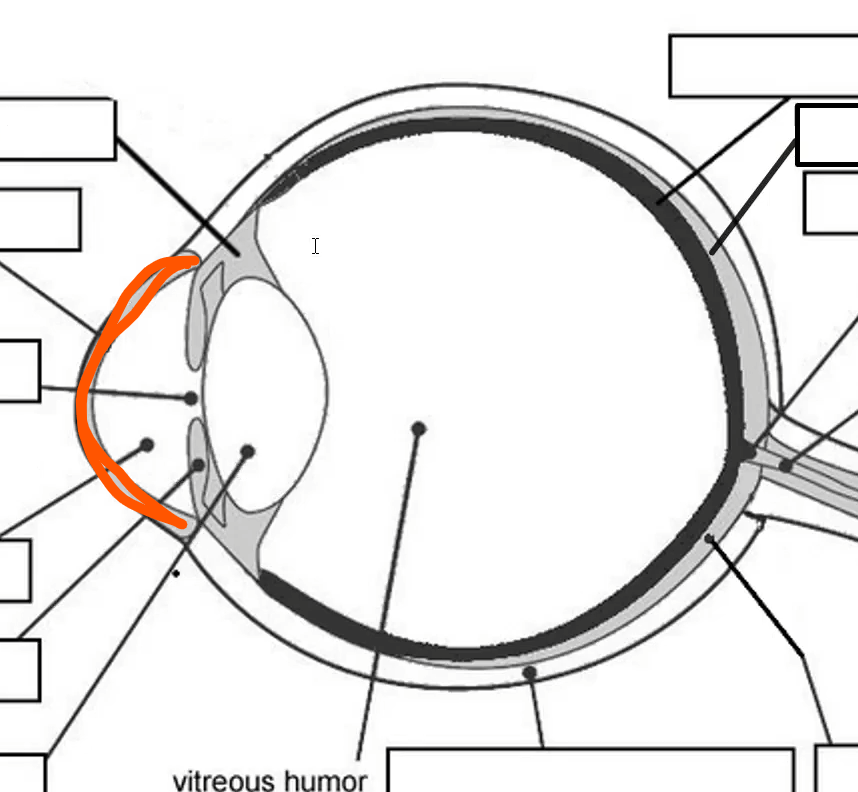

Name

cornea

allows light, most sensitive part of body

Name

Ciliary body

controls shape of lens

Name

Choroid

Name

Tapetum

Name

Optic nerve

Orange name

Retina

Orange

Iris

Blue

Pupil/lens

Red

Lens

Blue

Retina

Green

vitreous humor

Gray

Iris

Green

Sclera

Blue

Pupil

Orange

Anterior compartment

Maintains pressure